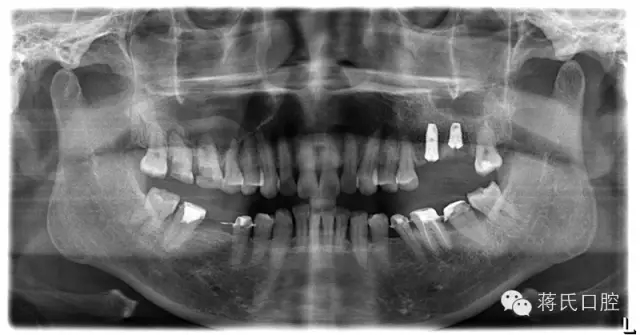

2.治療前口內(nèi)照片

8.種植后全景片